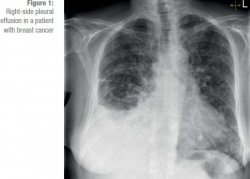

Mesothelioma Bilateral Pleural Effusion : Malignant Pleural Mesothelioma Radiology Case Radiopaedia Org : Pleural effusion is buildup of fluid between the chest wall and the lung.